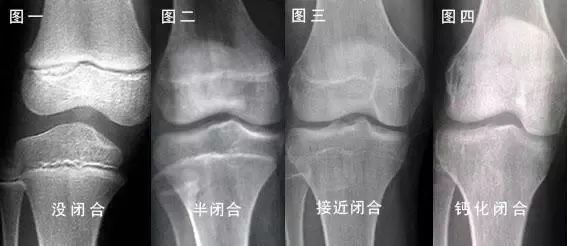

简单来说 , “骨骺线”完全闭合后 , 骨骼停止生长 , 人也就没法长高了 。

对不同的孩子来说 , 骨骺线闭合的时间也会有所差异 。

女孩一般闭合时间会比较早 , 在12-16岁左右;男孩一般比较晚 , 在16-18岁左右 , 有些可能更晚 。

骨骺线的闭合可以预知吗?

家长可以通过以下4个特征来判断:

- 生长缓慢或停止生长

- 性征发育成熟

- 体型明显变胖

- 肌肉逐渐结实

骨骺线一旦闭合 , 就目前的医疗手段基本无法干预 。 所以作为家长 , 我们要时刻注意孩子的发育状态 。

同时可以定期带孩子前往医院进行骨龄检测 , 通过骨龄片来观测孩子骨骺线的最新状态 。

如果发现孩子过早出现了骨骺线闭合的征兆 , 可以及时遵医嘱予以干预 。